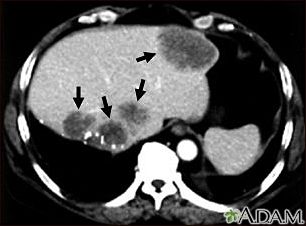

Liver metastases, CT scanBackLiver metastases, CT scanA CT scan of the upper abdomen showing multiple metastasis (cancer that has spread) in the liver of a patient with carcinoma of the large bowel. Note the dark areas in the liver (left side and center of picture). E-mail FormEmail ResultsName:Email address:Recipients Name:Recipients address:Message: